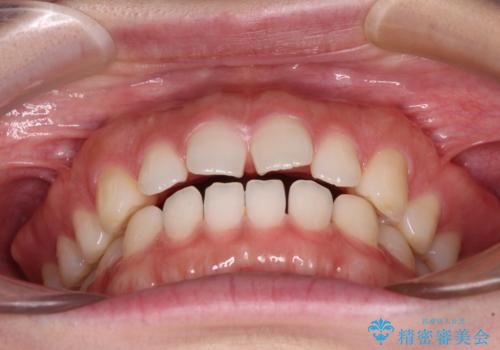

すきっ歯とオープンバイト インビザライン・ライトで改善

- 食いしばりによる顎の負担を気にして来院された患者様です。

当初は、ボツリヌス毒素による咬筋の過緊張の緩和と、睡眠時のマウスピース装着による咬合負担の解消を行いました。

オープンバイトのため、奥歯に負担のかかる咬合状態であったので、矯正治療を提案したところ、希望をされました。

すきっ歯程度の軽度の歯列不正であったため、インビザライン・ライトにより咬合改善を行うこととしました。